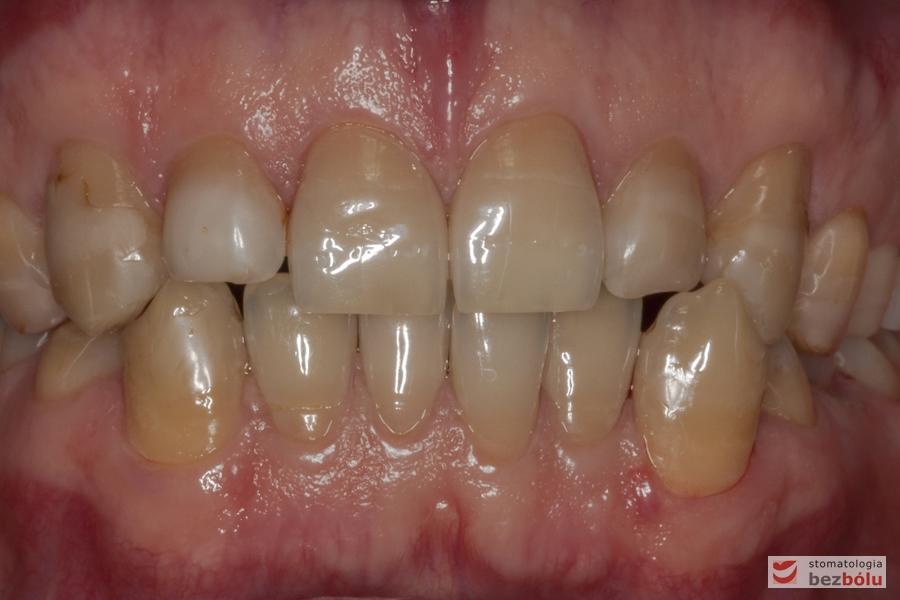

Zęby w zwarciu - widok frontalny, zaburzone relacje wielkości zębów, długości i szerokości

Zęby w zwarciu – widok frontalny, zaburzone relacje wielkości zębów, długości i szerokości